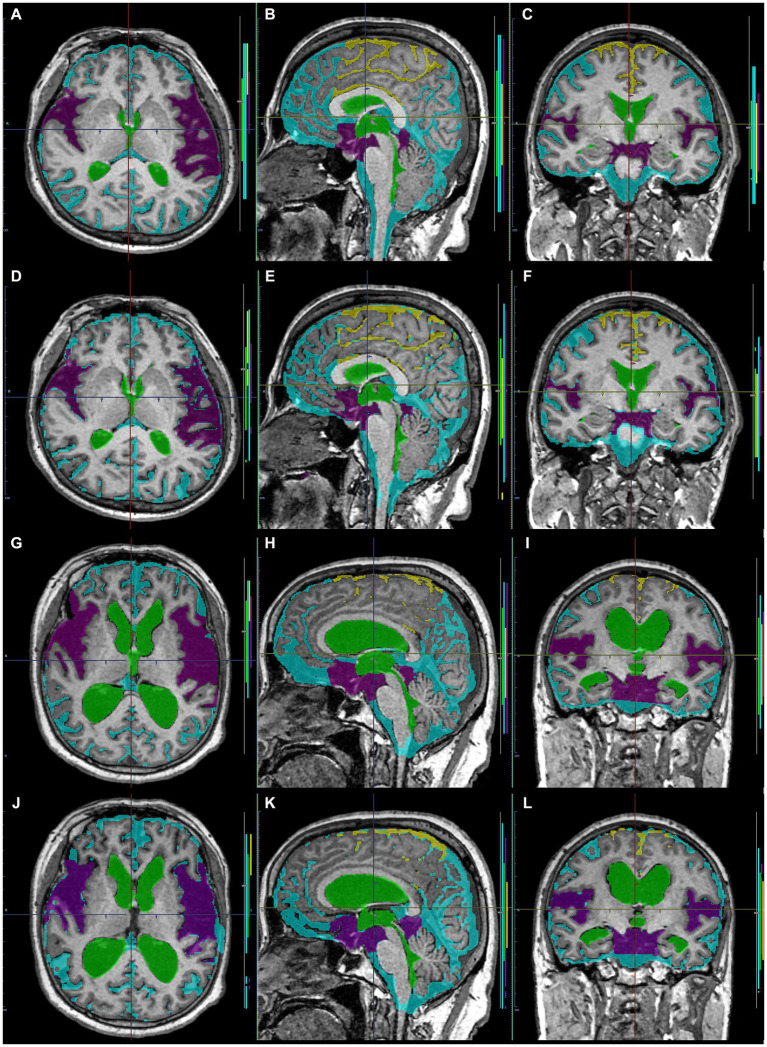

Preparation for data processing of deep learning

As ground truth labels in our AI models, input image masks for volumetric semantic segmentation on the 3D T1-weighted MRI were created by combining manual segmentation with the 3D Viewer and fully automatic segmentation with the Brain Subregion Analysis applications (Figures 1A–C) on an independent 3D volume analyzer workstation (SYNAPSE 3D; FUJIFILM Corporation, Tokyo, Japan). In the Brain Subregion Analysis application, intracranial spaces were segmented fully automatically into 26 subregions including ventricles and SAS within 1 min (ref. Yamada et al., 2023c). The input image masks from 3D T2-weighted MRI were also created using our original method, combining a simple threshold algorithm and manual segmentation (Figures 1D–F), as previously reported (ref. Yamada et al., 2015, ref. 2016a,ref. b). Total SAS were further segmented into the Sylvian fissure and basal cistern, and the high-convexity SAS, which was defined as the location above the body of the lateral ventricles, with the lateral end 3 cm from the midline, the posterior end in the bilateral posterior parts of the callosomarginal sulci, and the anterior end on the coronal plane perpendicular to the AC–PC line passing through the front edge of the genu of the corpus callosum (Figure 2; Supplementary Videos S1–S4) (ref. Yamada et al., 2023a). All input image masks as the ground truth labels were transferred to the SYNAPSE Creative Space for cloud-based AI development service (FUJIFILM Corporation). All masks were processed and formatted into a form that could utilize the training or inference process. Regarding the output of the inference process, feature maps were obtained. Overall, 159 T1-weighted images were assigned to 110 images for training, 30 for internal and 19 for external validation (test), and 180 T2-weighted images were assigned to 130 images for training, 30 for internal validation and 20 for external validation. Inference was performed in the images for internal validation and external validation.

Volumetric semantic segmentation

Training and internal validation of the 3D U-Net model for semantic segmentation were repeated over 1,000 times (Figures 4–7; Supplementary Figures S1, S2). Overall, the intracranial CSF space, total ventricles, total SAS, Sylvian fissure and basal cistern, and the high-convexity SAS were segmented fully automatically from 3D T1-weighted (Figure 8) and T2-weighted MRIs (Figure 9). There was no significant difference between manually and automatically segmented volumes of the total ventricles, total SAS, high-convexity SAS, and Sylvian fissure and basal cistern (Table 3). Among the segmented regions, the mean Dice scores for the total ventricles were highest (0.85 from T1 and 0.83 from T2), those for the Sylvian fissure and basal cistern were second highest (0.70 and 0.69), and those for the high-convexity SAS were lowest (0.68 and 0.60). The mean Dice coefficient scores for all of the regions segmented from the T1-weighted image were superior to those from the T2-weighted image. The mean differences between the manually and automatically segmented volumes of the high-convexity SAS were smaller (T1 and T2; 3.6 mL and 4.2 mL) than those of the Sylvian fissure and basal cistern (5.3 mL and 8.3 mL).